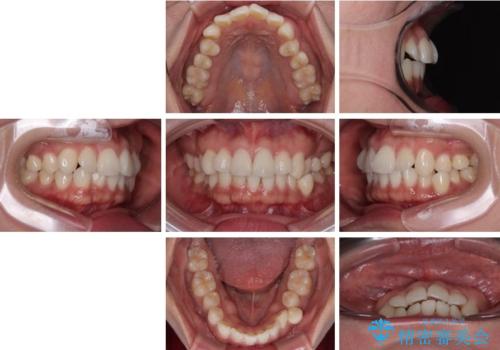

- 「歯並び全体のデコボコが気になる」「上下の歯の正中(中心)がずれているのが気になる」

このようなお悩みを主訴にご来院された患者様の矯正治療症例をご紹介します。

初診時、上下顎ともに歯列の不正が認められ、特に左下の小臼歯が大きく歯列から外れている状態でした。その影響により、下顎の正中が左側へシフトしており、見た目だけでなく噛み合わせにも影響が出ていました。